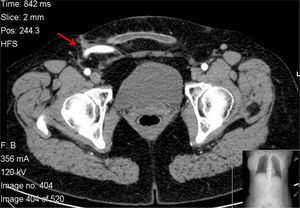

We report a case of a 45-year-old female patient, submitted to femoro-femoral bypass two months before, who was admitted at our institution with a tender mass on the right groin associated with local and systemic signs of infection. Angio-CT scan showed an occluded stent in the right iliac artery and two femoro-femoral bypasses in place with only one functioning and a 8.3cm collected abscess in the right femoral region (Fig. 1) in close contact with the prosthetics grafts. There were no signs of hemorrhage or false-aneurysms.